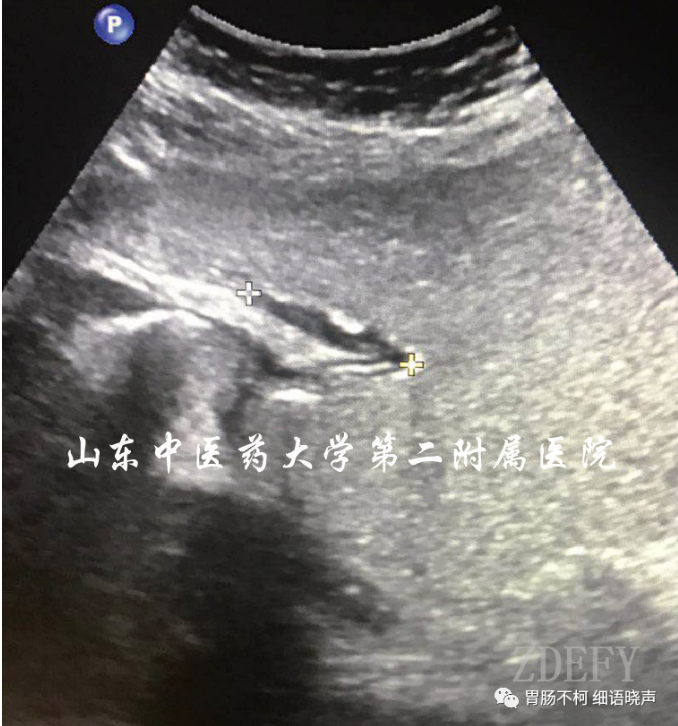

但在应用的时候,应注意不典型病例带来的鉴别困扰。比如胃壁因炎症水肿增厚明显,易导致良性溃疡与“土堆挖坑征”不易鉴别;浸润溃疡型胃癌的溃疡,易表现为“平地挖坑征”;愈合期溃疡与浸润溃疡型胃癌的鉴别有困难。无论典型不典型,抓住细节特征,最终将其鉴别开来。思考一下:以下几个溃疡,其良恶性鉴别点在哪里?